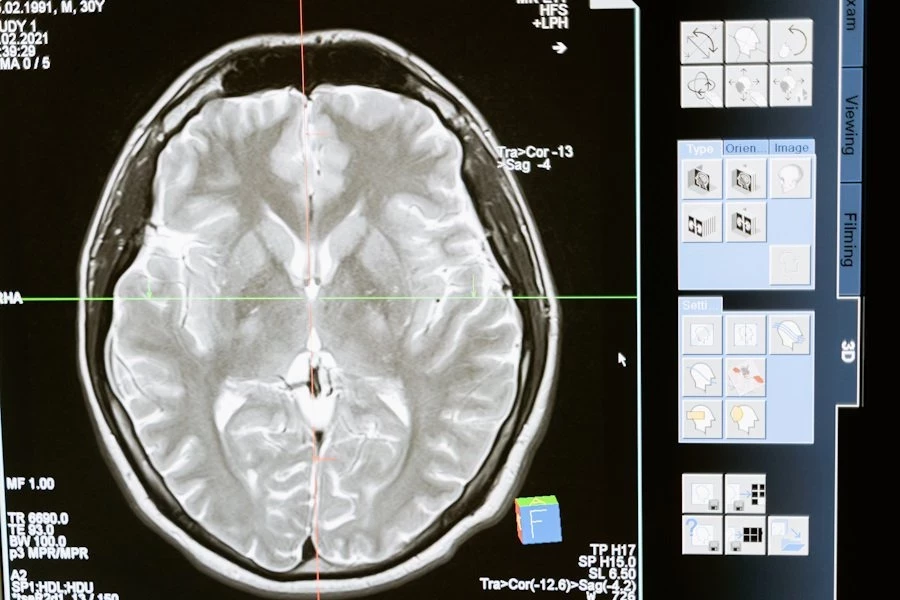

Ученые из Memorial Sloan Kettering Cancer Center (США) добились значительного прорыва в лечении глиобластомы — одной из самых агрессивных форм рака мозга. Ими была идентифицирована молекула глиоцидин, способная избирательно уничтожать клетки глиобластомы, не повреждая при этом здоровые ткани организма, сообщает Nature.